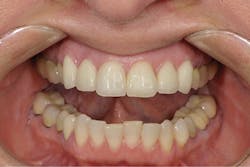

A 52-year-old female patient presented to my office with recent porcelain restorations that had been placed on her upper six anterior teeth. Besides her complaint of the bite feeling different, her main concern was that her speech was off, especially her s sounds. She stated these problems occurred after the final crowns were placed. Further questioning also revealed that she was unhappy with color and shape (figures 1–3). A full examination was completed, including x-rays and photographs, and periodontal, TMJ, occlusion, and dentition evaluations. She had excellent oral health and her dental issues were all related to her occlusal and esthetic complaints.

Figure 2: Anterior retracted view of the patient’s original restoration